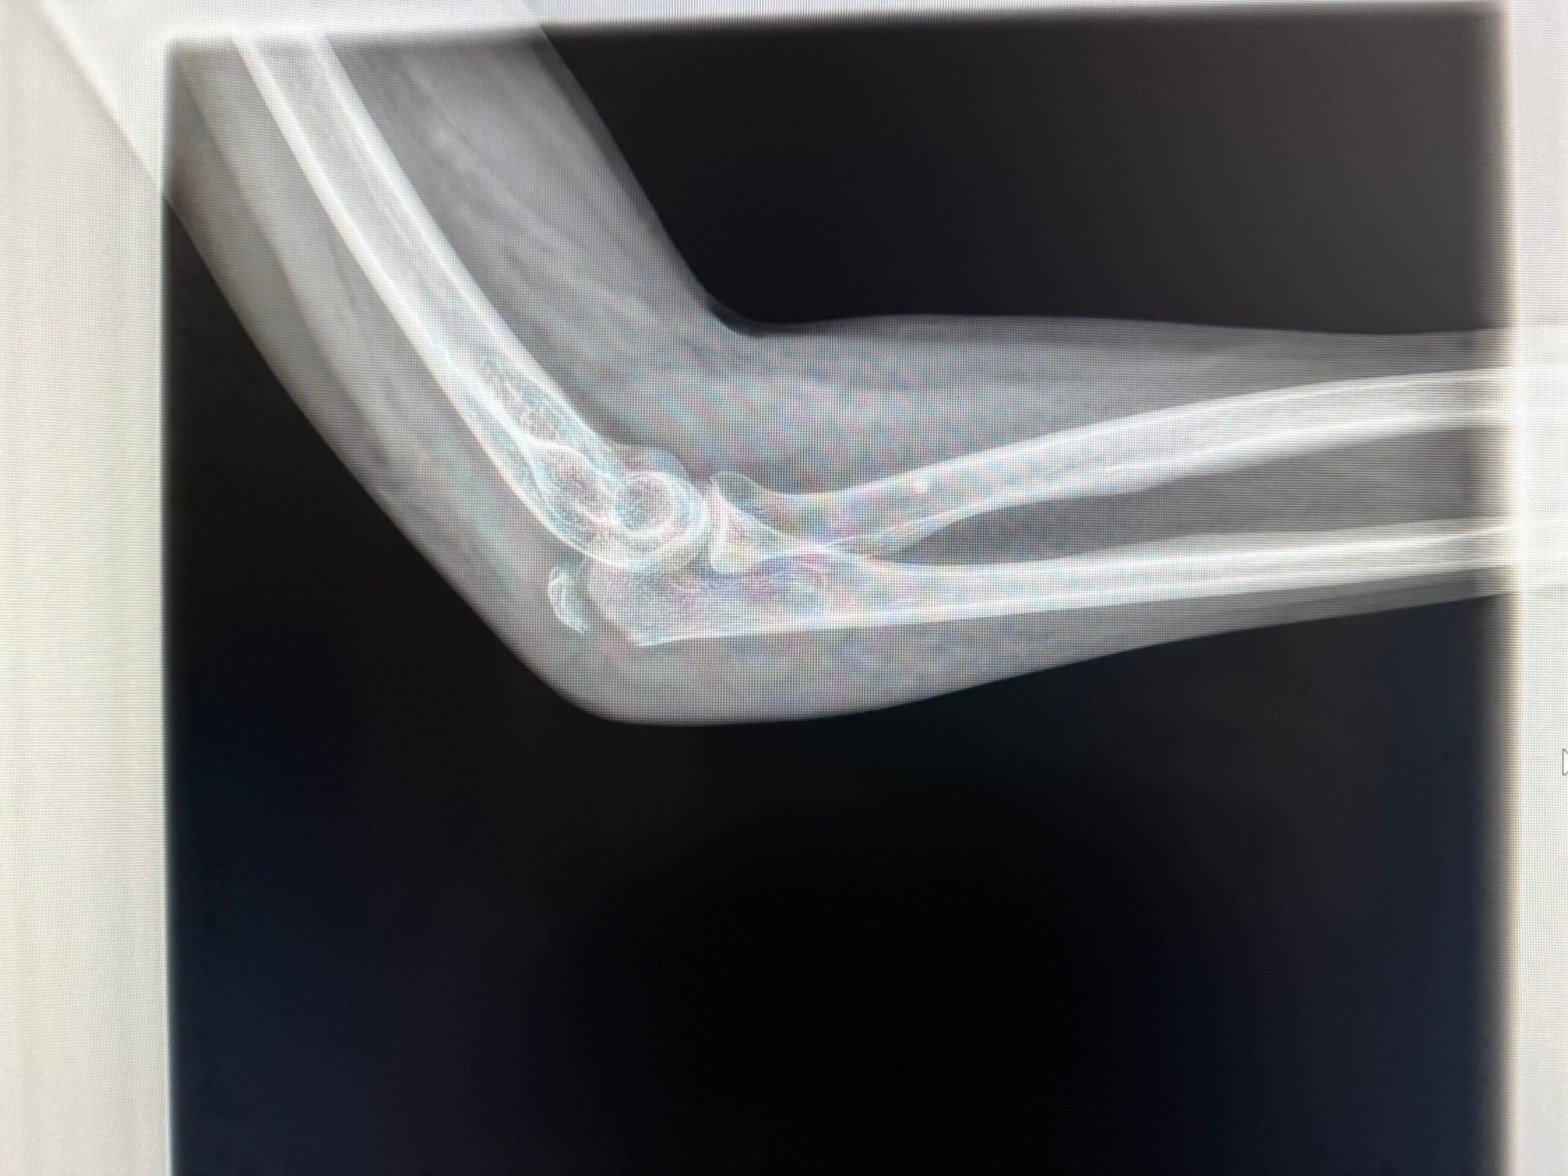

Today’s unfortunate post is curtesy of a set of rain slick steps combined with my clumsiness. A little over one week ago I slipped on a set of 3 steps, fell backwards & did this to my left elbow (thankfully not my dominant arm). As today’s not so fun, fun fact, I broke my elbow on the last day of my vacation while I was getting ready to drive back home. Yes, friends, I drove 10 hours home by myself with a hurt back (which bothered me much more than the elbow) & broken elbow. In my defense, I’d convinced myself I hadn’t broken anything. I was quite the sight. I probably worried the people who saw me at the rest stops & gas stations. I’m surprised no one passed me a note asking if I was okay.

Speaking of work, obviously I’m limited in what I can do there as well. It is suspected that it will be 3-4 months (at least) before I can do surgery again. It’s amazing how fracturing just a tiny piece of bone impacts your life. Apparently, the triceps tendon attaches to the olecranon (that tiny, pointy piece of your elbow that I fractured). I’m scheduled for surgery this Tuesday to reattach the tendon.